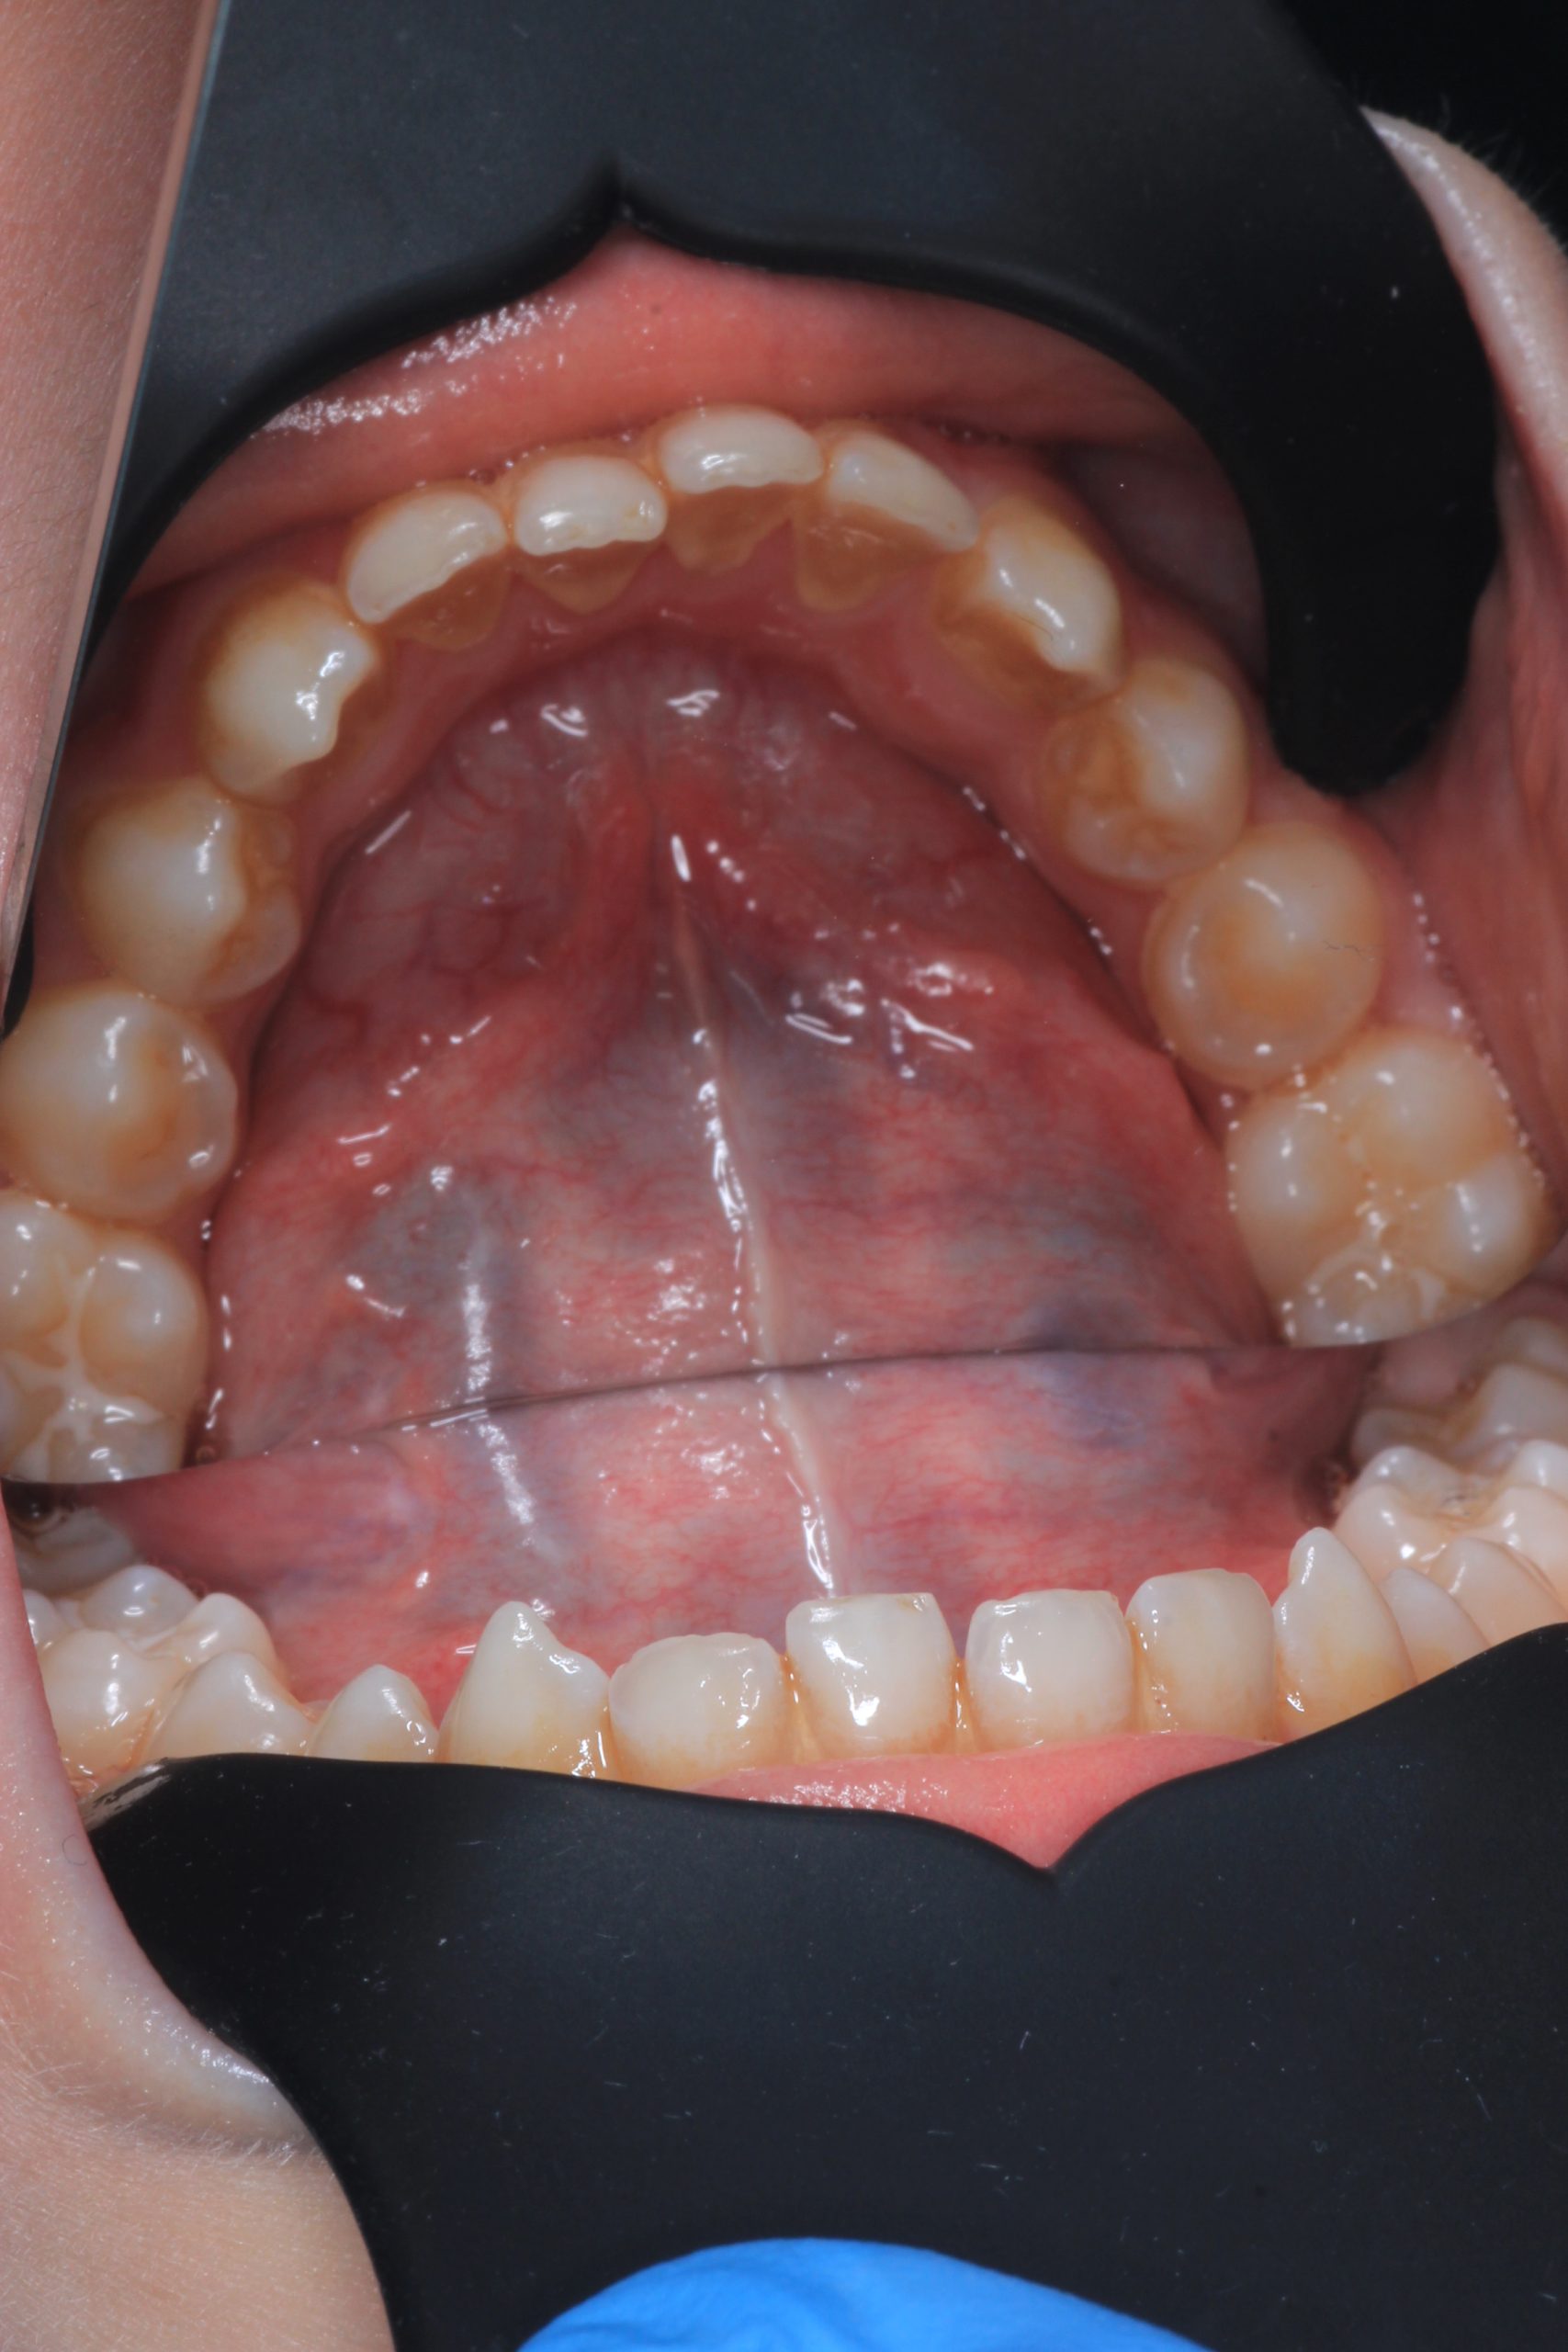

We examine the condition of teeth, gums, and bite. - Plaque Disclosure with Special Indicators

Areas that weren’t cleaned well appear purple. The darker the shade, the older the plaque. This helps both kids and parents understand where brushing needs to improve. - Brushing Training & Home Care Tools Selection